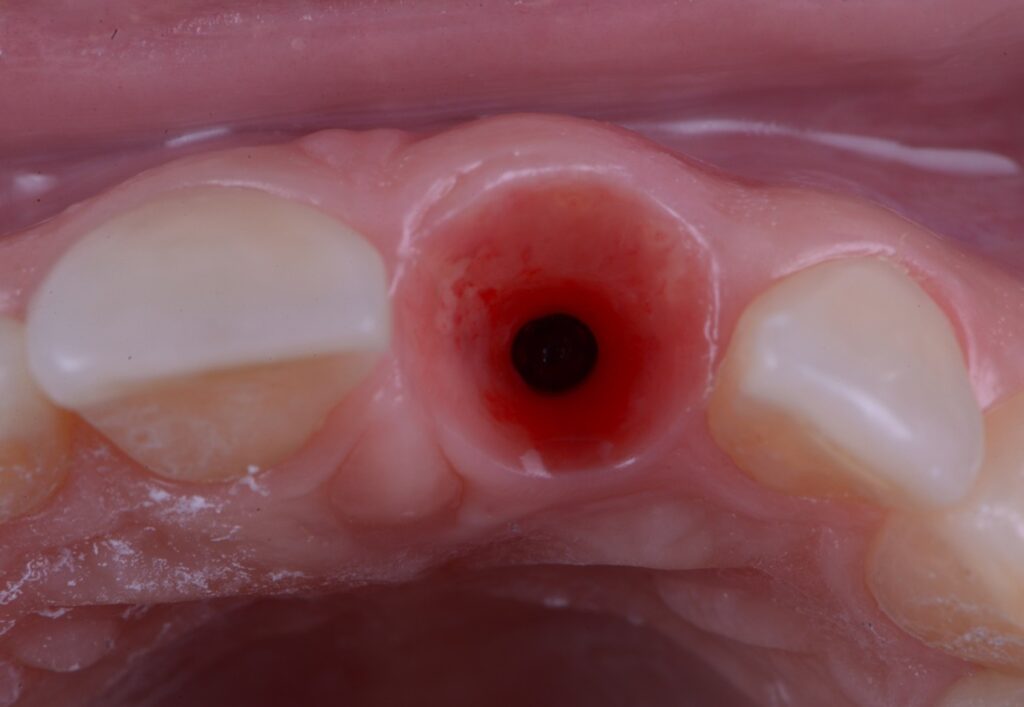

Fig. 2: Implant placed into the fresh extraction socket in the correct 3D position ( Straumann BLX Roxolide SLActive 3.75×12)